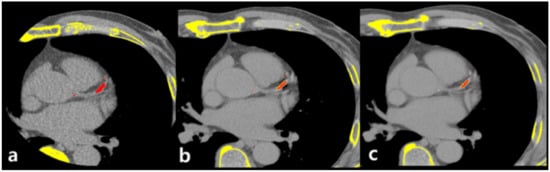

CT scan was performed in two steps: all patients underwent ECG-gated coronary calcium-scoring CT first and then underwent non-ECG-gated contrast-enhanced dual-energy chest CT (Figure 2).

CT Image Reconstruction and Analysis

After scanning enhanced chest DECT, Gemstone Spectral Imaging data, GE’s dual-energy techniques for acquiring and generating material density data using rapid kV switching and Gemstone Detector technology, were stored in an image processing workstation (AW Server 3.2, GE Healthcare, Chicago, IL, USA) and reconstructed into 70 keV virtual monochromatic images with 1.25 mm and 2.5 mm slice thicknesses that were most similar to conventional 120 kVp polychromatic CT images [21,22,23] (Figure 2B). VUE images were then obtained using the material suppressed iodine (MSI) technique (Figure 2C).

Figure 2. Process of image acquisition. First, ECG-gated non-enhanced calcium-scoring CT was performed (a). Subsequently, non-ECG-gated contrast-enhanced dual energy chest CT was performed with reconstructed virtual 70keV monochromatic images, which are similar to 120-kVp images (b). Finally, virtual unenhanced images were acquired with the material-suppressed iodine technique (c).